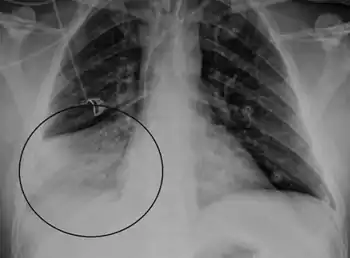

Pneumoviruses are pleomorphic, capable of producing spherical and filamentous, enveloped virions (virus particles) that vary in size from 150 to 200 nm in diameter. The nucleocapsid consisting of a protein shell and viral nucleic acids has a helical symmetry. Nucleocapsids have a diameter of 13.5 nm and a helical pitch of 6.5 nm.[6]